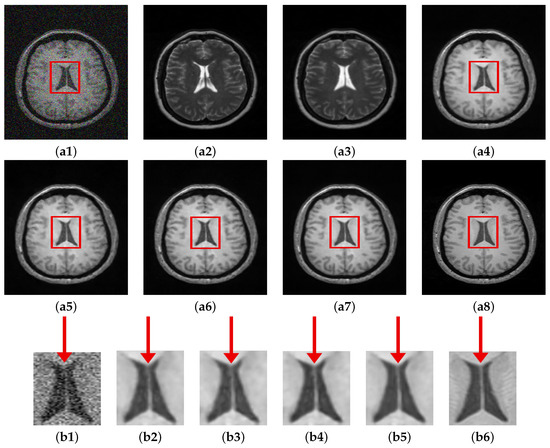

To better understand the motivation of using cross-modal guidance information, the guidance image was bypassed and a noisy T1 image was fed to both branches of the PHL module as explained in Section 3.4. The results of this setup and its comparison with other variants of the proposed method are shown in Figure 9. Visually, the denoised images are similar on the whole; however, the enlarged ROI shows slight structural differences among the results. The model trained using identical noisy images fed to both branches (without guidance image) fails to recover various structures of the input image. Both C M G D N e t r s and C M G D N e t s s yield better results compared to the T1-T1 configuration; however, they also lack in recovering some structural information. C M G D N e t r g shows better performance compared to the three variants in terms of retaining structural similarity with the ground truth. Incorporating SSIM in the registered configuration, that is C M G D N e t s g configuration performs best. It not only retains structural similarity to a considerable extent, moreover, it also gives sharp edges compared to all the other variants. The PSNR-SSIM values for all the configurations tested are shown in Table 7.

Figure 9. Comparison of proposed method (different configurations). (a1) Noisy. (a2) Unreg. T2. (a3) Reg. T2. (a4) C M G D N e t r s . (a5) C M G D N e t s s . (a6) C M G D N e t r g . (a7) C M G D N e t s g . (a8) GT, Corresponding enlarged RoI: (b1) Noisy. (b2) C M G D N e t r s . (b3) C M G D N e t s s . (b4) C M G D N e t r g . (b5) C M G D N e t s g . (b6) GT.